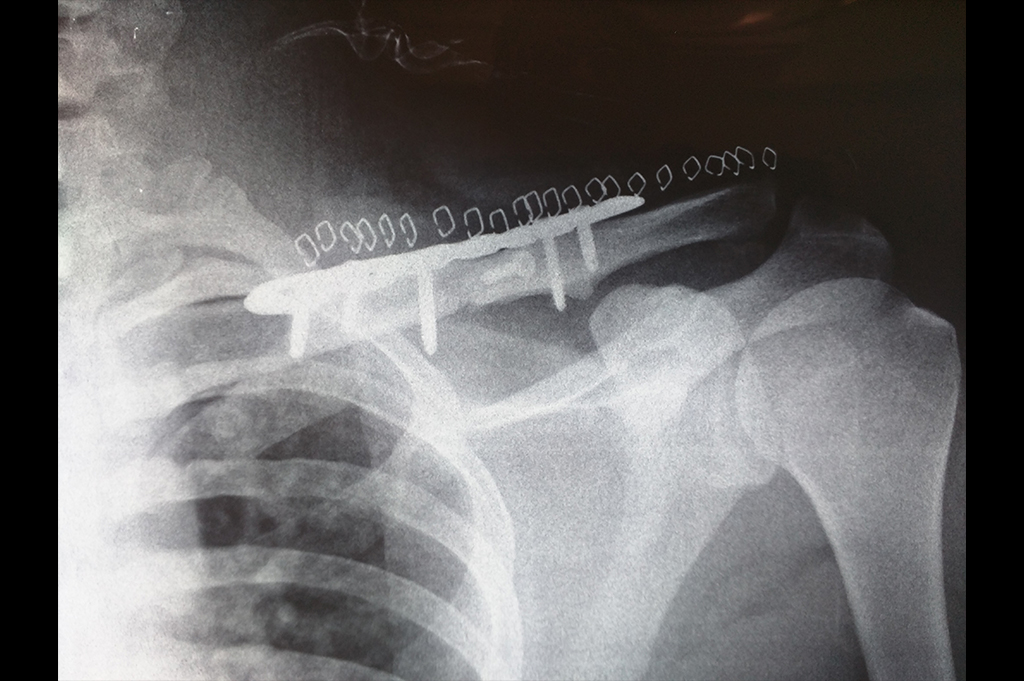

Clavicle